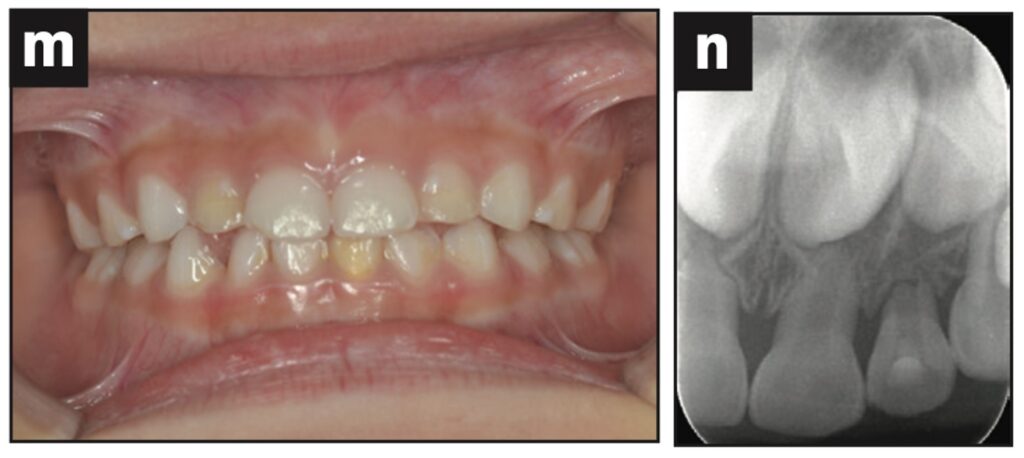

Bệnh nhân là một bé gái 5 tuổi bị ngã đè lên chai nước khi đang uống nước và bị bật răng cửa sữa bên trái ra ngoài. Nhân viên chăm sóc trẻ đã rửa răng bằng nước máy và làm sạch chất bẩn trên răng, loại bỏ màng nha chu.

Răng được đặt lại và cố định bằng composite quang trùng hợp, sau đó lấy dấu. Bệnh nhân quay lại phòng khám nha khoa 3 tiếng sau đó và nhận khay duy trì.

Dặn dò phụ huynh để cho bệnh nhân phải đeo hàm duy trì cả ngày trừ lúc đánh răng. Răng được kiểm tra sau 1, 7, 14 và 21 ngày và chụp X quang sau 28 ngày. Điều trị nội nha được thực hiện sau khi răng đã ổn định.

Quá trình theo dõi 12 tháng trong giới hạn bình thường (hình 1f).